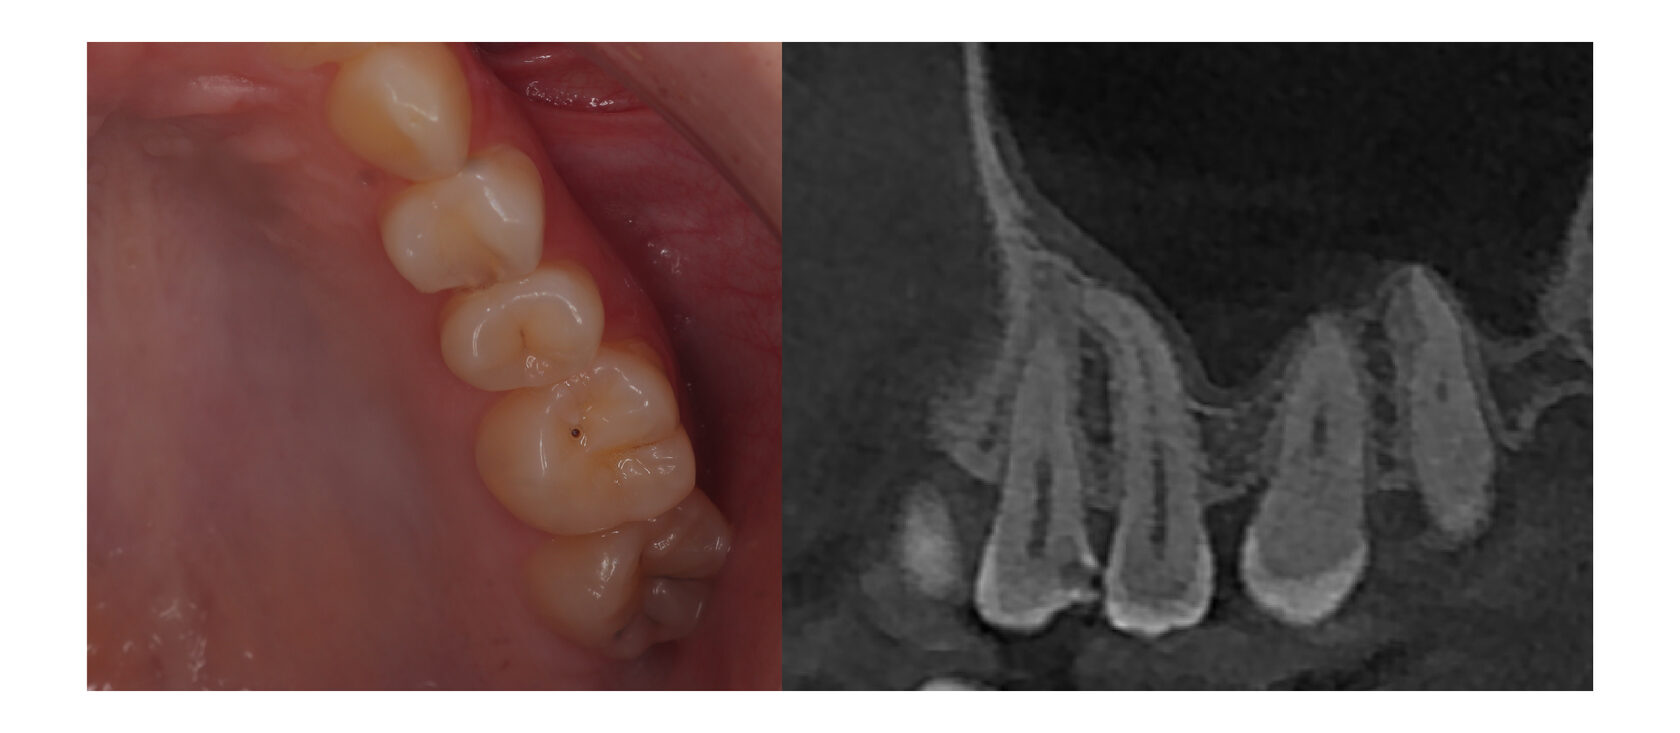

Но пациент на данном этапе не начал лечение, в связи с тем, что зуб не беспокоил. Спустя 1,5 года пациент обратился уже с жалобой на постоянную ноющую боль в этом же зуба, которая мучала его все новогодние праздники! Не самое приятное ощущение, правда?

При осмотре и на снимке мы видим уже совсем другую картину. кариозная полость сильно углубилась и достигла нерва, поэтому зуб давал такую сильную боль.